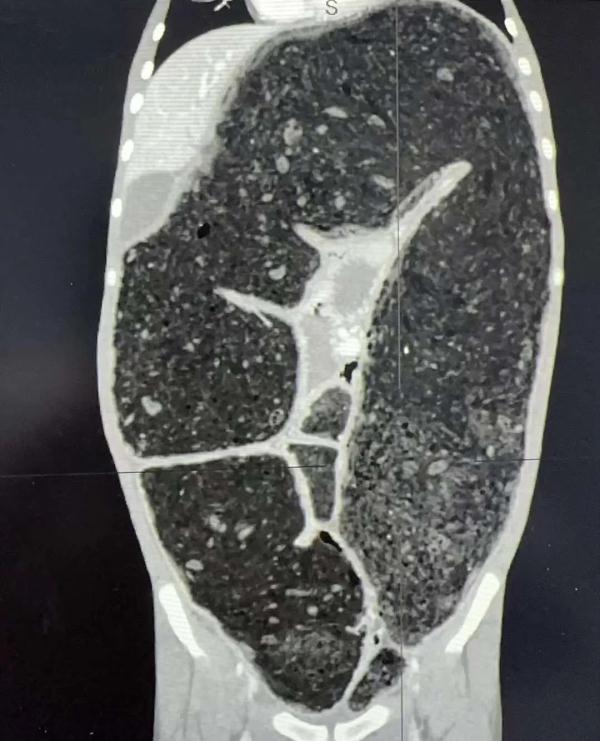

ct示大量粪便和扩张结肠

小远入院后,医生考虑到他存在先天性巨结肠合并肠炎,当即给予禁食禁水、抗感染、灌肠和肛管减压等保守治疗。但由于痉挛肠管较长、扩张肠管内容物过多,导致排空不畅,洗肠效果不佳。两天后,小远出现了腹胀加重、端坐呼吸、感染指标升高。普通(新生儿)外科副主任李颀仔细查看后,评估小远病情危重,存在早期感染中毒性休克(巨结肠危象),感染来源是异常扩张的结肠和肠内容物,手术刻不容缓,决定在当天也就是5月6日进行急诊手术。